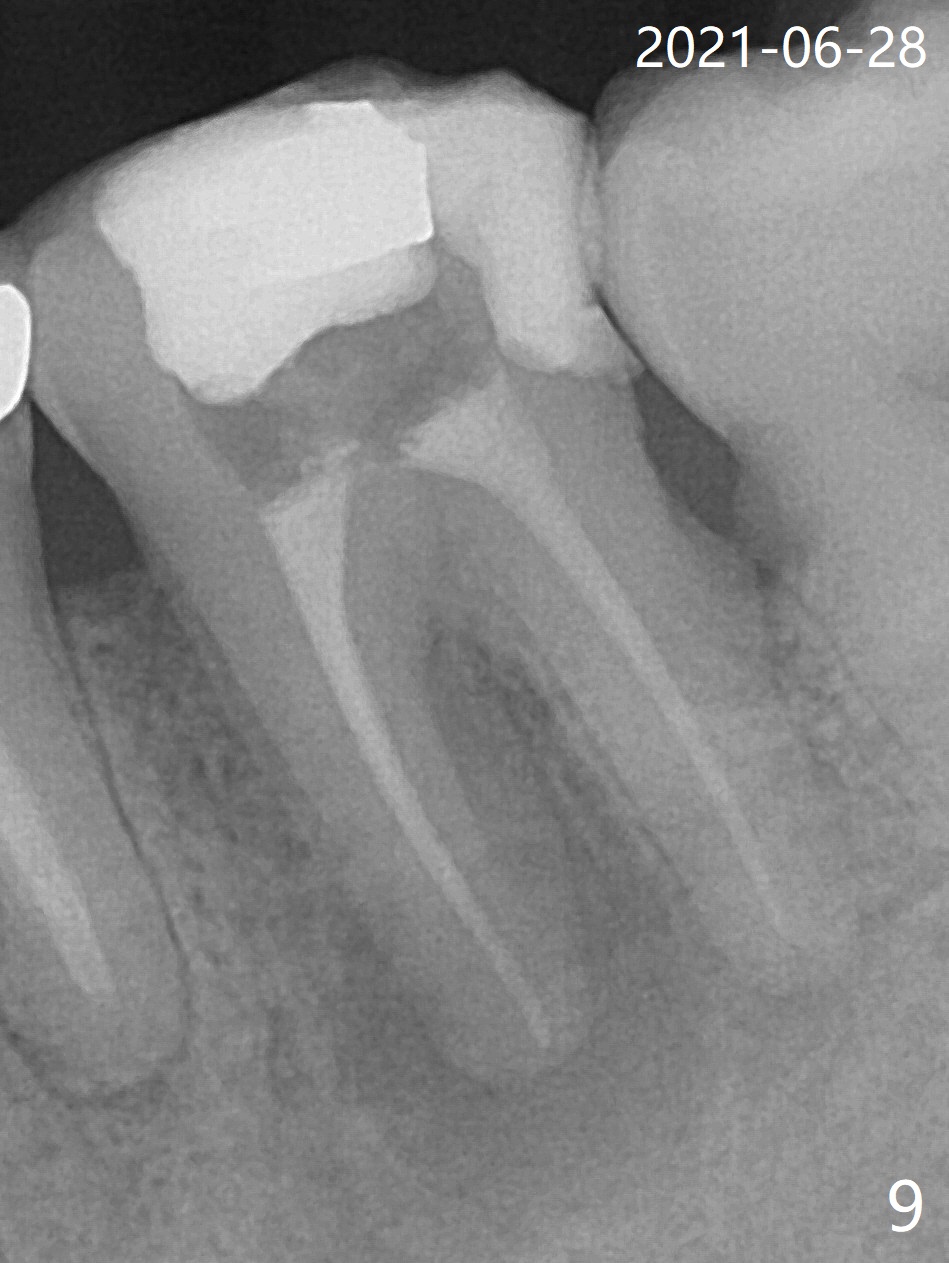

Designed osteotomy depth is 7.3 mm IS drill with 4 rings at #15. In fact osteotomy is created using 2.2 mm drill with 2 rings (sinus membrane barely visible from the osteotomy) and 3-4 mm ones with 3 rings. With an amalgam carrier of bone graft, sinus lift is initiated with 4x9 mm dummy implant (Fig.1). After loaded with totally 5 amalgam carriers of bone graft repeatedly with the 4x9 mm dummy implant, a 5x9 mm implant is placed with ~ 25 Ncm. After insertion of a 6x4(2) mm abutment, sticky bone cut into pieces (Fig.2) is inserted to peri implant space (Fig.3 *), followed by PRF and an immediate provisional. The latter dislodges 7 days postop; the socket starts to heal (Fig.4); the bone graft seems to be fixed in place. The provisional is reseated (no cement, Fig.5) without fear of its dislodgement again. The patient returns for cleaning 1 year 7 months postop (Fig.6,7). The socket heals, while the abutment is incompletely seated (Fig.7 <). Percussion at #18 disappears post RCT, whereas periapical radiolucency appears post RCT (compare Fig.8,9). When the 6x4(2) mm incompletely seated abutment is removed, the implant well is dirty. The smaller abutment with longer cuff is seated fully (Fig.10).